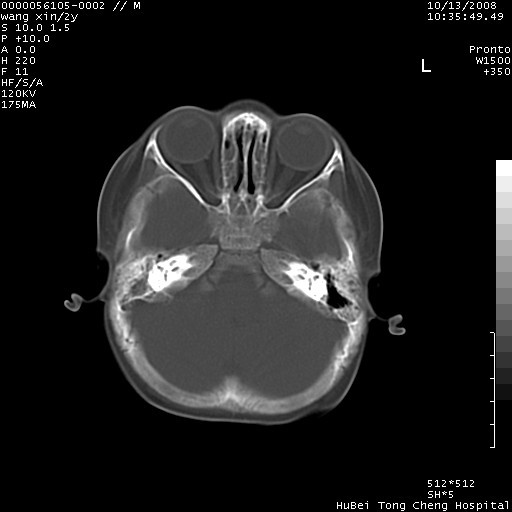

标题: PED1611:F,2Y。右侧额部小包块,光整,质硬,边界清楚,无 [打印本页]

标题: PED1611:F,2Y。右侧额部小包块,光整,质硬,边界清楚,无

病灶临近颅缝,支持考虑表皮样囊肿可能,病灶区要薄扫就好了

右额骨内板压迫性变薄,呈椭圆形膨胀性骨吸收和低密度区,其间可见小斑片状致密影,-支持表皮样囊肿

考虑右侧额骨表皮样囊肿.双侧上颌窦\\筛窦炎.